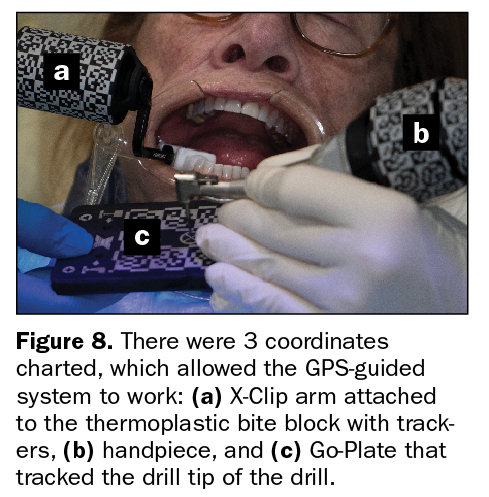

Browse our specialized Calibration In Dynamic Navigation Surgery In Implamt portfolio with numerous expertly curated photographs. optimized for both digital and print applications across multiple platforms. providing reliable visual resources for business and academic use. Each Calibration In Dynamic Navigation Surgery In Implamt image is carefully selected for superior visual impact and professional quality. Perfect for marketing materials, corporate presentations, advertising campaigns, and professional publications All Calibration In Dynamic Navigation Surgery In Implamt images are available in high resolution with professional-grade quality, optimized for both digital and print applications, and include comprehensive metadata for easy organization and usage. Our Calibration In Dynamic Navigation Surgery In Implamt collection provides reliable visual resources for business presentations and marketing materials. Whether for commercial projects or personal use, our Calibration In Dynamic Navigation Surgery In Implamt collection delivers consistent excellence. The Calibration In Dynamic Navigation Surgery In Implamt archive serves professionals, educators, and creatives across diverse industries. Regular updates keep the Calibration In Dynamic Navigation Surgery In Implamt collection current with contemporary trends and styles. Advanced search capabilities make finding the perfect Calibration In Dynamic Navigation Surgery In Implamt image effortless and efficient. Multiple resolution options ensure optimal performance across different platforms and applications.